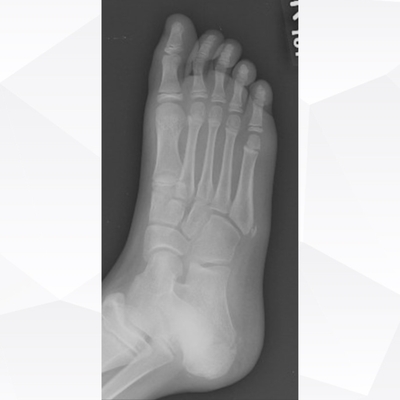

Click on an image below to view more info.